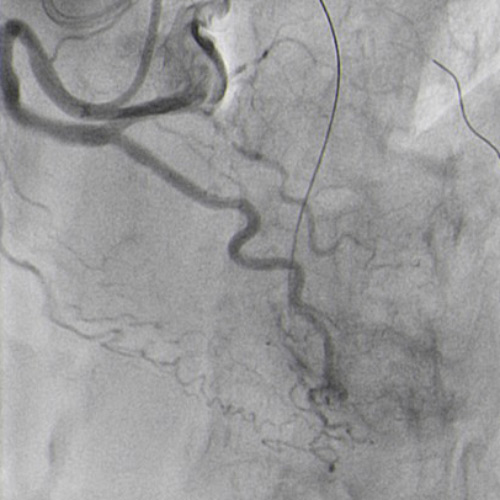

Double radial access with guiding catheter 6F JR 4.0 and sheatless 7.5F PB 3.5. Controlateral injection to check antegrade wire position via collaterals (Figure 4.1).

CTO crossed with Miracle 6g, after unsuccessful attempts with Sion and Pilot 150. Floppy wire in diagonal branch to improve support (Figure 4.2).